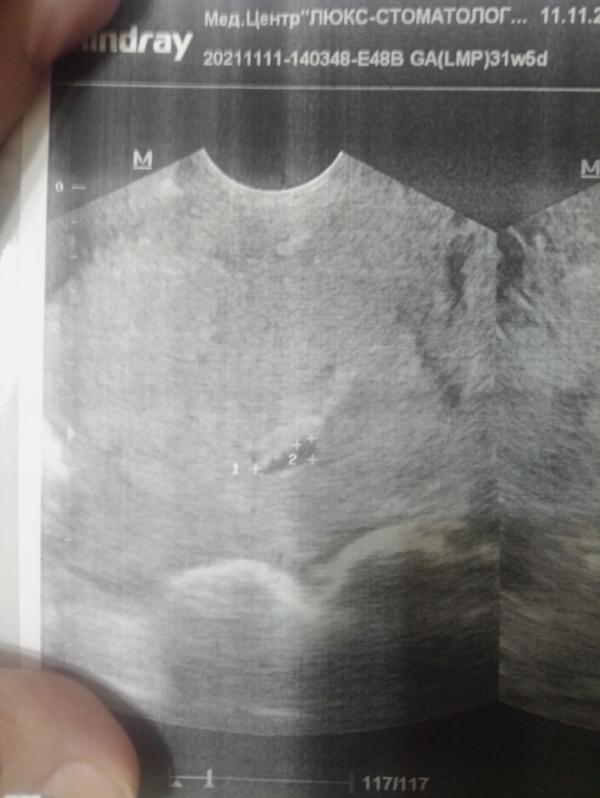

Всем привет! Девочки, была на узи, сказали плодное яйцо какое то приплюснутое, прийти через недельку. У кого было похожее что то? Срок примерно 5.5 недель

Сердечко есть